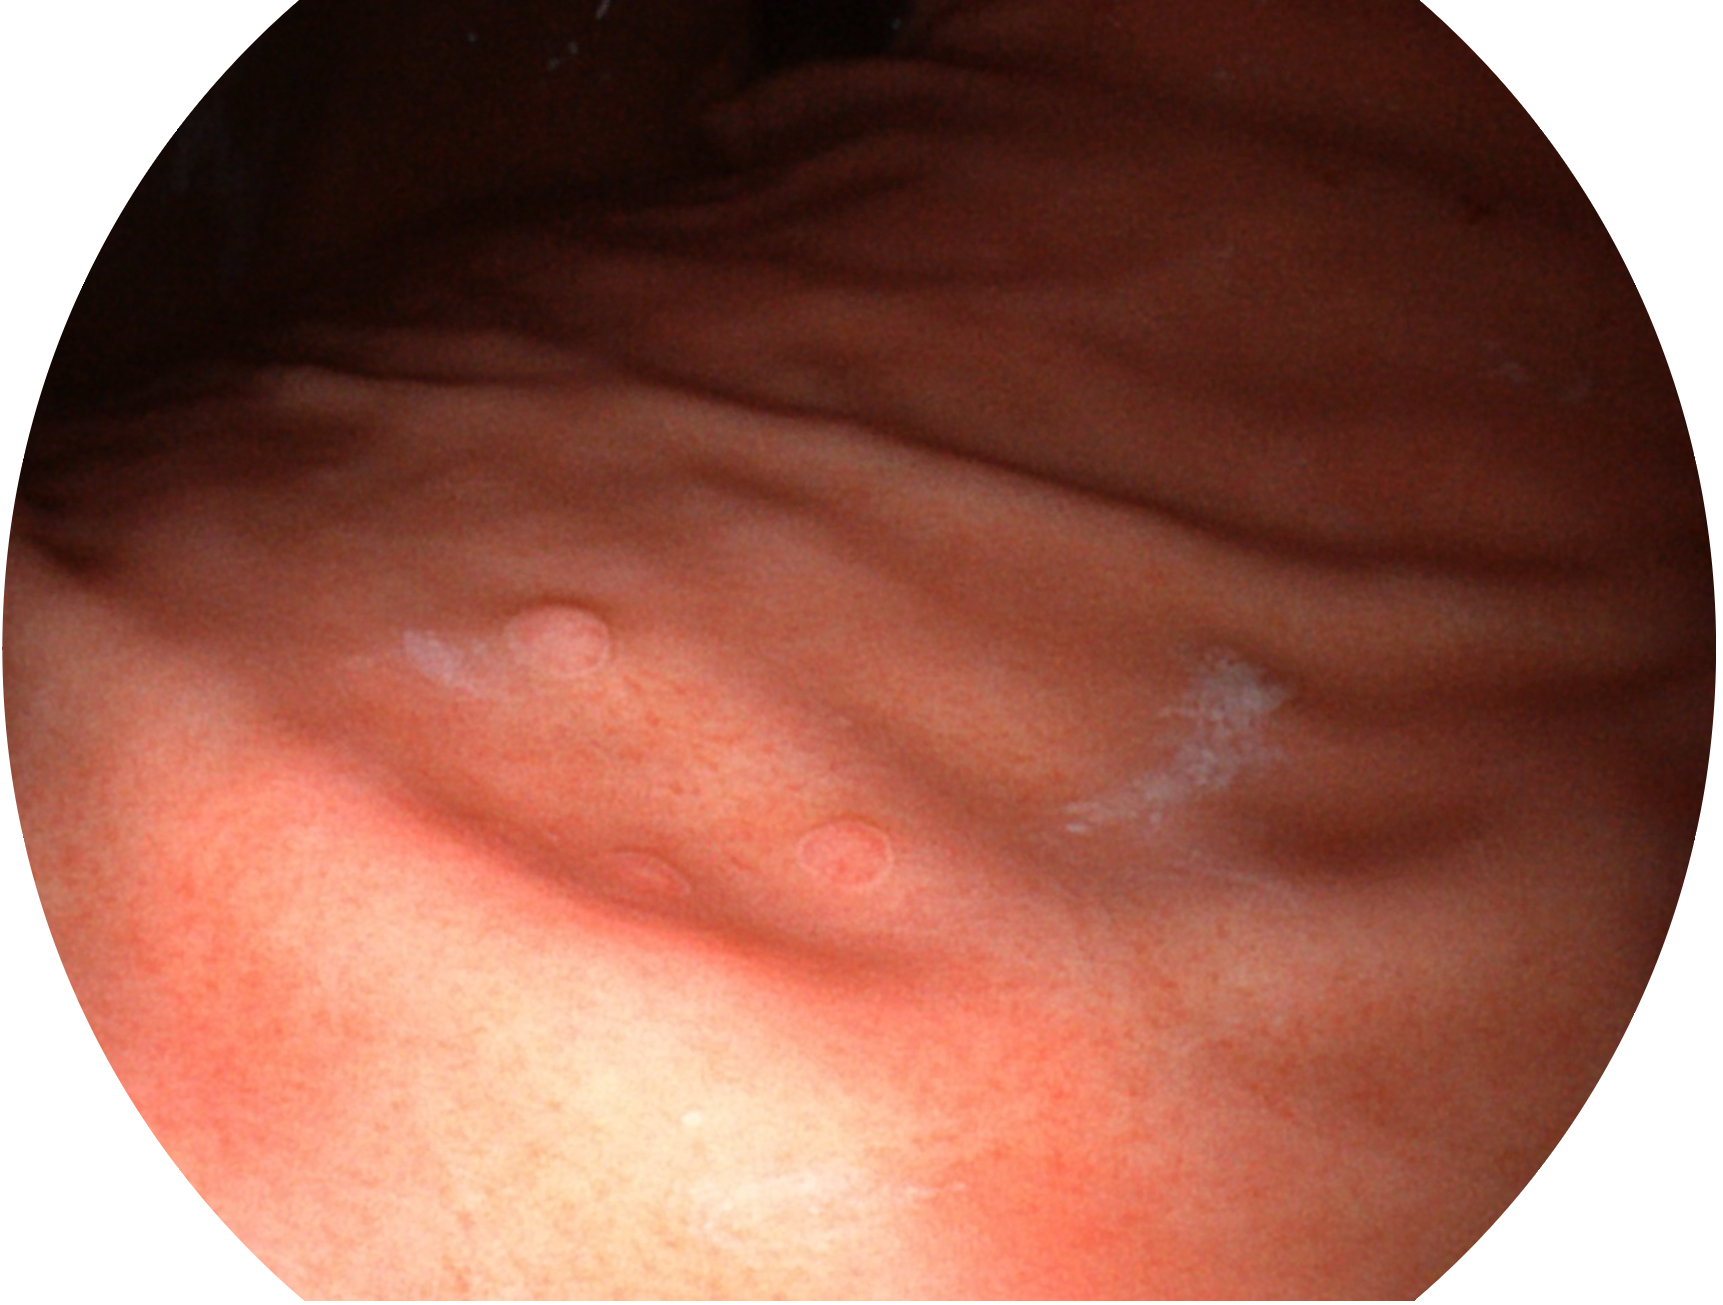

開立新開發(fā)的內(nèi)鏡染色技術(shù),主要是基于多波長LED 光源的開發(fā),VLS-55Q 四波長LED 光源是由四個不同顏色的LED光按照相應(yīng)照明模式所規(guī)定的特定發(fā)光比例進(jìn)行合束后形成,合束后形成的照明光的光譜由紅光、綠光、藍(lán)光及藍(lán)紫光這四個不同的波段范圍構(gòu)成。具有更高光譜自由度,通過光譜比例的控制,實現(xiàn)了聚譜成像技術(shù),英文全稱為“Spectral Focused Imaging, SFI”,縮寫為“SFI”和光電復(fù)合染色成像技術(shù),英文全稱為“Versatile Intelligent Staining Technology, VIST”,縮寫為“VIST”。